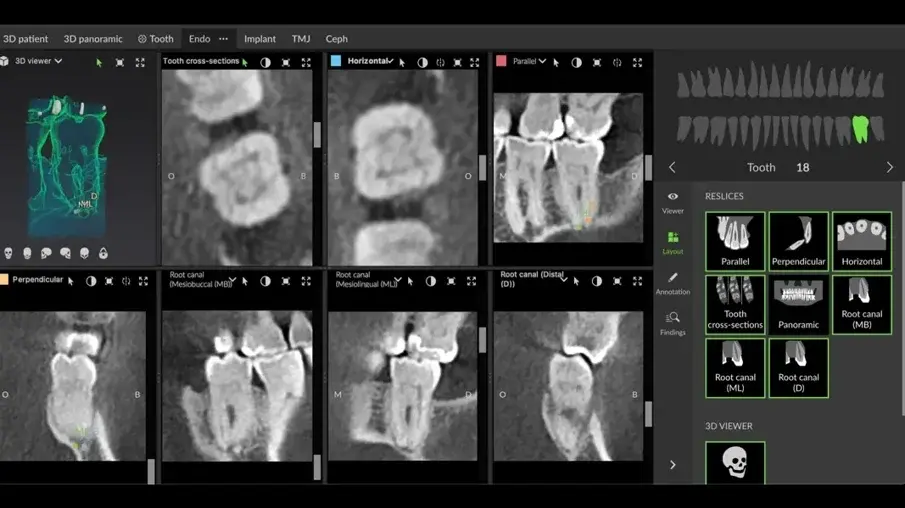

Ендодонтският режим в новия софтуер DTX Studio Clinic позволява добавянето на много изгледи и профили и регулирането на дебелината на разрезите с цел проверка на нивото на калцификация. Допълнително предимство е, че той позволява проследяване на вътрешната анатомия на корените, заедно и поотделно. При проследяване на кореновите канали може да се избере цвят за всеки канал. Това е от голяма полза за онагледяване на вътрешната анатомия (фиг. 3)

Фиг. 3 Ендодонтският режим в DTX Studio Clinic проследява анатомията на каналите и предоставя приблизителна работна дължина в различни цветове за всеки канал. Изобразени са четири отделни корена.